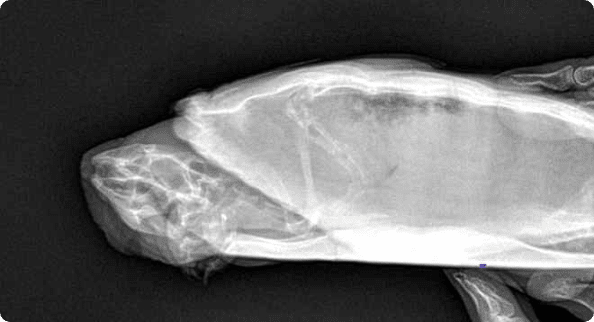

피부질환, wet tail 같은 소화기 문제의 내과질환부터

햄스터 자궁축농증 수술, 종괴제거 수술, 알막힘 등 다양한 질환을 치료합니다.